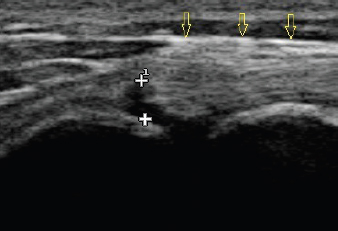

Fig. 1. Longitudinal ultrasound image of an acutely torn biceps tendon (yellow arrows). The tear itself can be seen as an absence of fibers between the two “+” symbols.

When addressing bicipital tendon tears or tenosynovitis, conservative therapy still remains the treatment of choice, as it preserves the tendon and retains function (Millis and Levine, 2013; Leeman et al., 2016; Zink and Van Dyke, 2018). Such options include analgesics, cryotherapy, exercise restriction, therapeutic ultrasound, extracorporeal shockwave therapy, laser, massage, intra-articular corticosteroids, intra-articular platelet-rich plasma, and stem cell therapy (Millis and Levine, 2013; Leeman et al., 2016; Zink and Van Dyke, 2018). To date, there is limited data on the effectiveness of these treatments. Leeman et al. (2016) demonstrated that 85% of the patients receiving extracorporeal shockwave therapy for either biceps, supraspinatus, or combined biceps and supraspinatus tendon pathology, had good or excellent outcomes based on subjective owner assessment. Although regenerative medicine techniques incorporating cultured stem cells, bone marrow aspirate concentrate, or adipose-derived stromal vascular fraction have not been investigated as a treatment for biceps tendon pathology, they have shown positive outcomes when used to address either canine supraspinatus tendon or cruciate ligament injury (Canapp et al., 2016a, 2016b). This paper’s primary author has experienced positive outcomes using combined platelet-rich plasma and bone marrow aspirate concentrate when addressing biceps tendon pathology (Figs. 1 and 2).